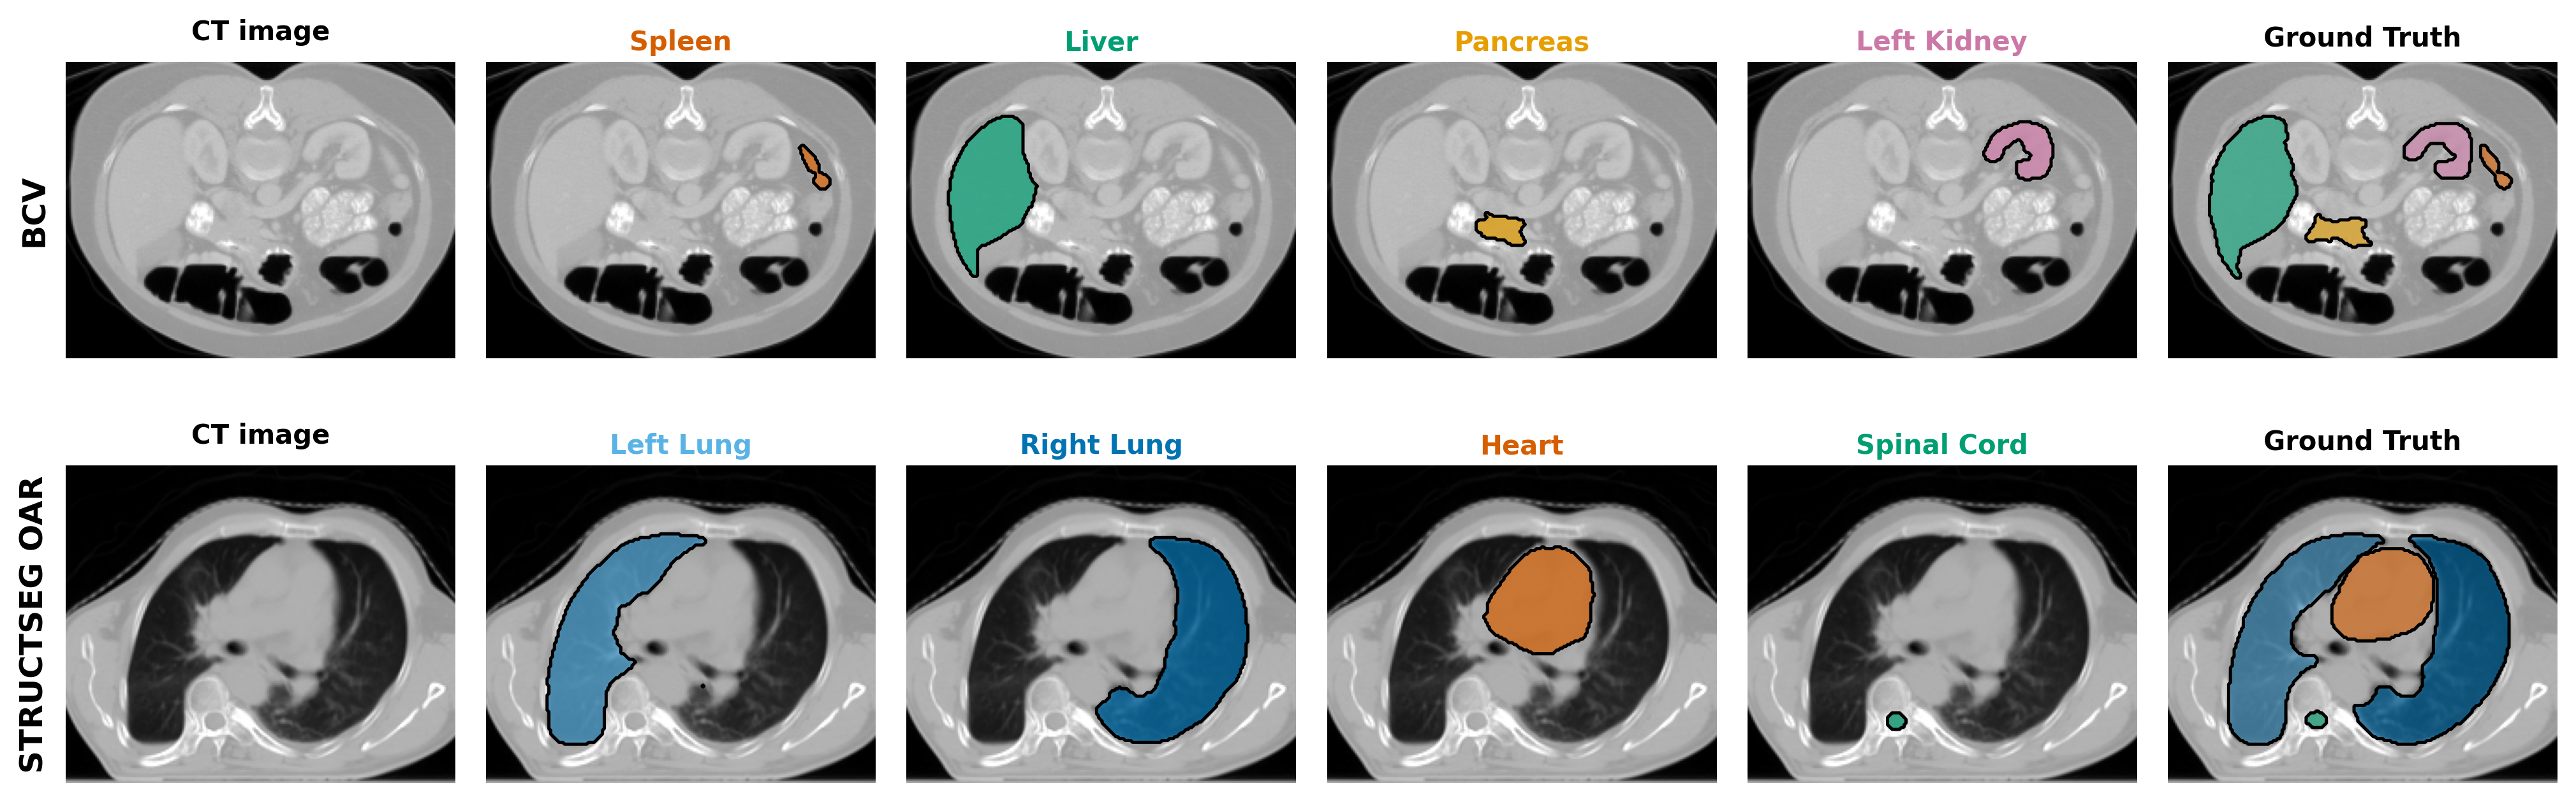

Refer to caption

Figure 4: Cross-modality organ segmentation using modality-aware text prompts. Rows show the same abdominal organs segmented from CT (top, AMOS CT) and MR (bottom, AMOS MR) images. The model uses dual prompts: T1 specifies the modality/region context, while T2 targets specific organs. By adapting T1 to the imaging modality (”computed tomography” vs ”magnetic resonance”), the model successfully segments the same anatomical structures across both modalities without modality-specific training.

The qualitative results in Figure 3 and Figure 4 visually validate the effectiveness and flexibility of our dual-prompt architecture. They specifically showcase the model’s precise, on-demand target control and its robust adaptability across different imaging modalities and organs.

The versatility of the framework across modalities is demonstrated in Figure 4. By only modifying the context prompt, T1T_{1}, to reflect the imaging modality (“computed tomography” versus “magnetic resonance”), DuPLUS successfully segments the same set of abdominal organs in both CT and MR images. This proves that the model effectively leverages the contextual information in T1T_{1} to adapt its feature extraction process, confirming its ability to generalize to diverse clinical imaging data. Collectively, these visual examples provide strong qualitative support for our quantitative findings and validate the hierarchical, text-controlled design of DuPLUS.